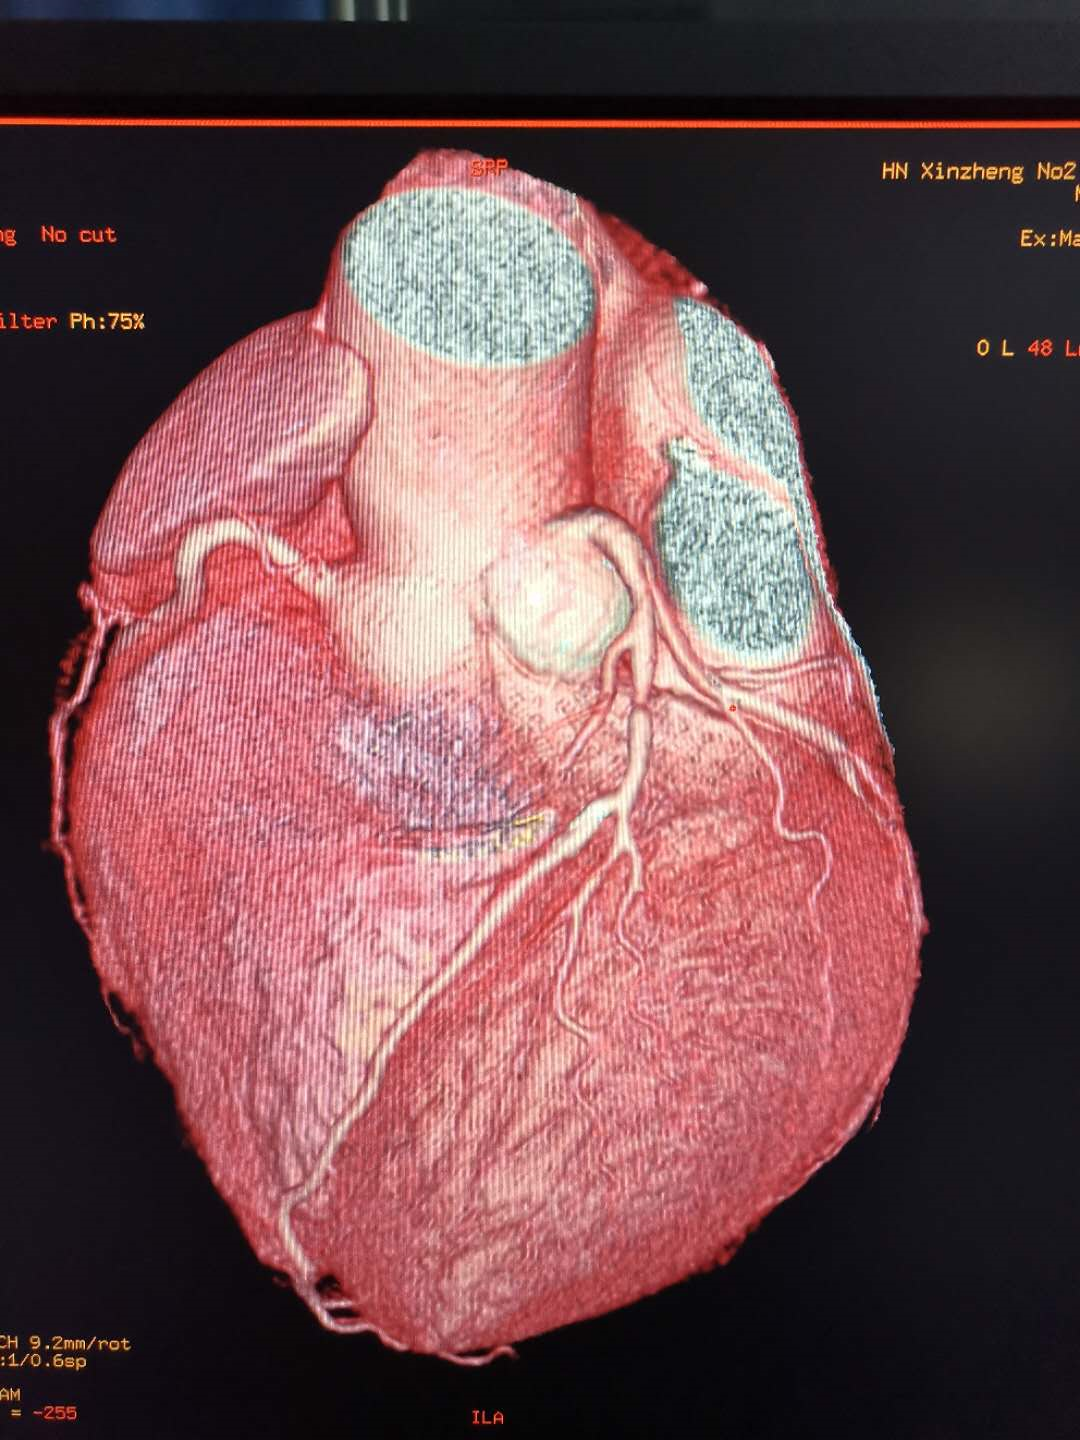

要想排除冠心病诊断,首选冠脉CTA 冠脉CTA检查,是一种特殊的增强CT扫描,只要图像清晰,诊断无误,排除冠心病诊断的准确率高达99%。除此以外,目前其他任何的心脏检查均不能排除冠心病的诊断。

冠脉支架植入术后或搭桥术后的复查

以往支架植入术后的复查需要再次做造影复查。现在应用冠脉CTA复查,简单方便。